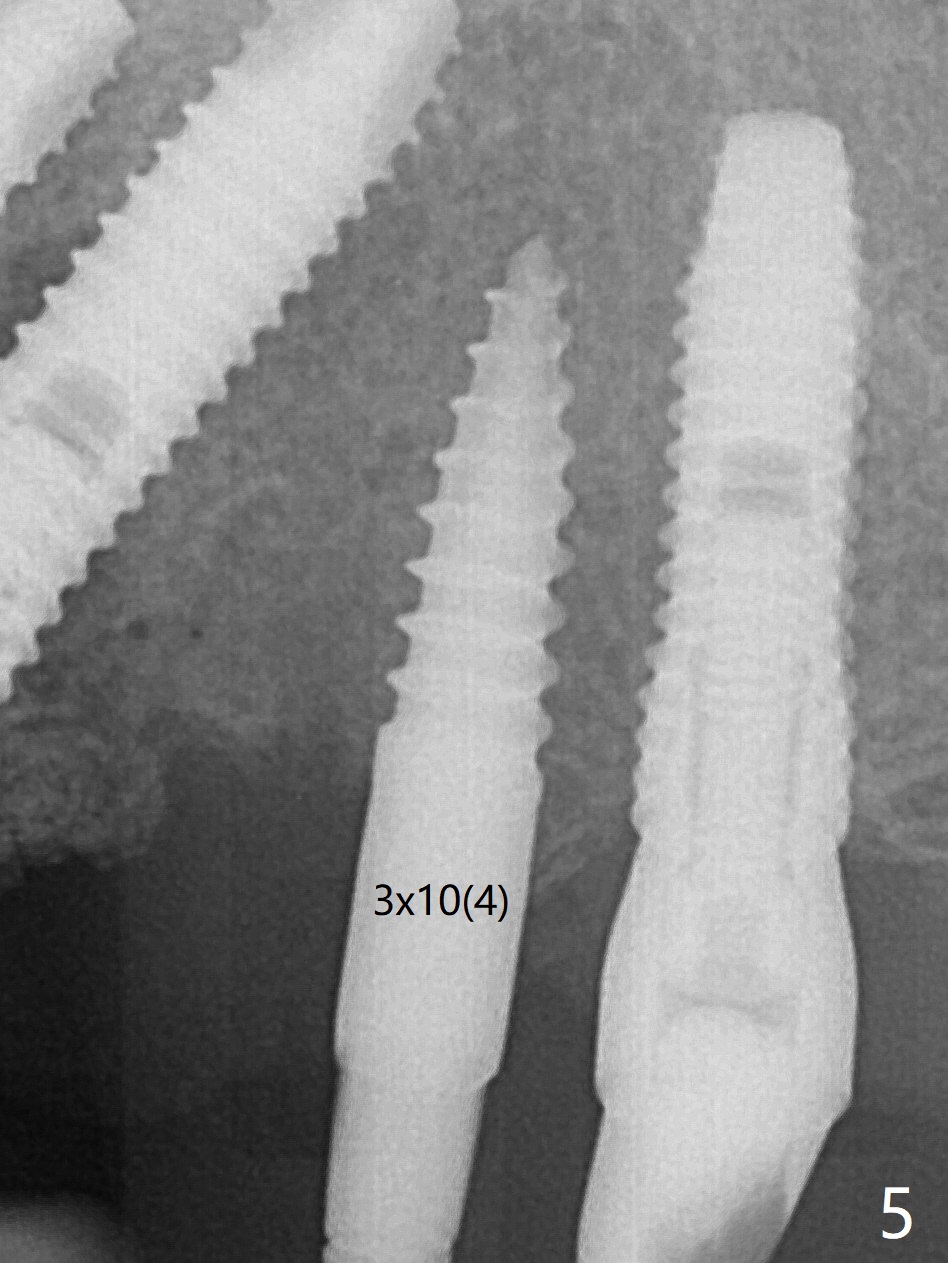

A 48-year-old man returns to clinic with fractured FPD 1 year 5 months post cementation (temp bond, Fig.1,7). It appears necessary to add an implant at #13 site (Fig.2). The narrow ridge is reduced to start an osteotomy (Fig.3 *). After change in osteotomy position and trajectory (Fig.4), a 3x10(4) mm 1-piece implant is placed (Fig.5). With deeper placement of the implant (Fig.6 arrow), cortical bone graft is placed (*).